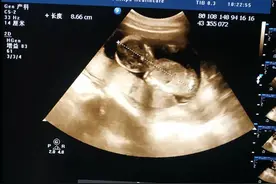

孕妈怀孕五个月了,前一阵子跟婆婆一起去医院照B超。因为抵挡不住宝宝到底是男是女的好奇心,于是找熟人看了胎儿性别。得知腹中胎儿是女孩,孕妈挺开心,因为自己跟宝爸都喜欢女孩,连女孩的名字都起好了。婆婆也强作笑脸说,男女都行,只要健康就好,再说还可以生二胎。

1,双顶颈大于22,PH值73,中性细胞比一直高4,妊娠线到胸口,又细又直,上线与下线到肚脐是错开的5,头胎女儿肚子软,二胎硬实,最主要平躺肚脐是个小坑6,胎动满肚子动,有时拳打脚踢7,胎心130—1408,胎梦不准,整个孕期都是男孩胎梦9,35周先兆早产见红10,整个孕期只胖肚